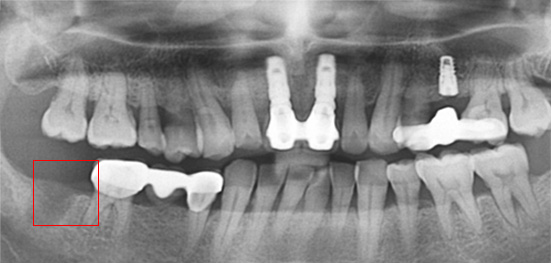

아래턱 어금니 발치 후 장시간 방치하여 잇몸 뼈 소실이 심한 상태로 내원. 뼈 이식 후 임프란트를 식립하였습니다.

잇몸 뼈 소실이 심한 상태로 내원

뼈 이식 후 치조골 밀도가 높아진 모습